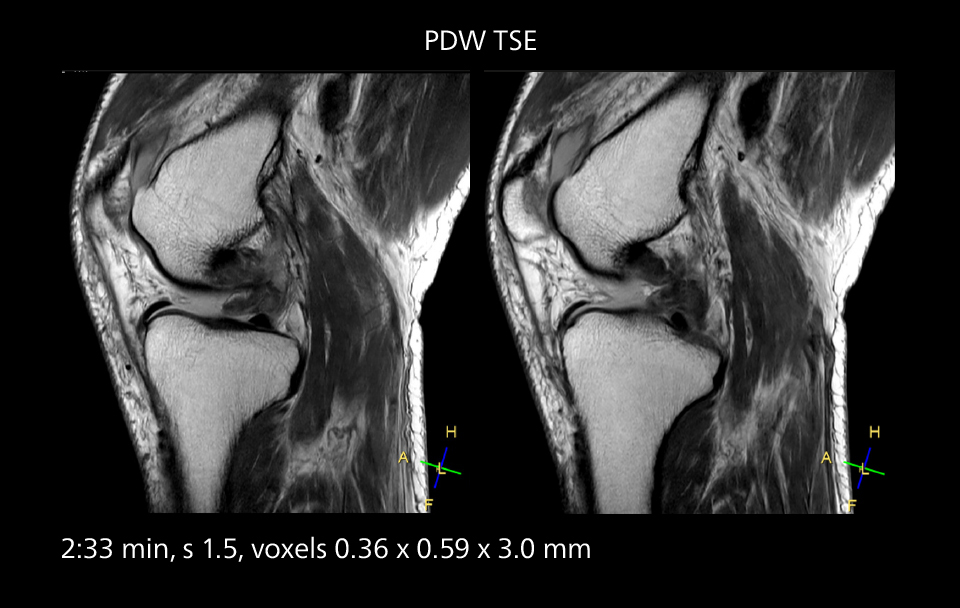

MRI of the knee

Images showing a posterior cruciate ligament (PCL) tear, a detached medial collateral ligament (MCL) on the tibial side and an intact anterior cruciate ligament (ACL). SmartPath to Elition X helped reduce scan time compared to previous imaging while maintaining resolution.

MRI of the knee

Images showing a posterior cruciate ligament (PCL) tear, a detached medial collateral ligament (MCL) on the tibial side and an intact anterior cruciate ligament (ACL). SmartPath to Elition X helped reduce scan time compared to previous imaging while maintaining resolution.